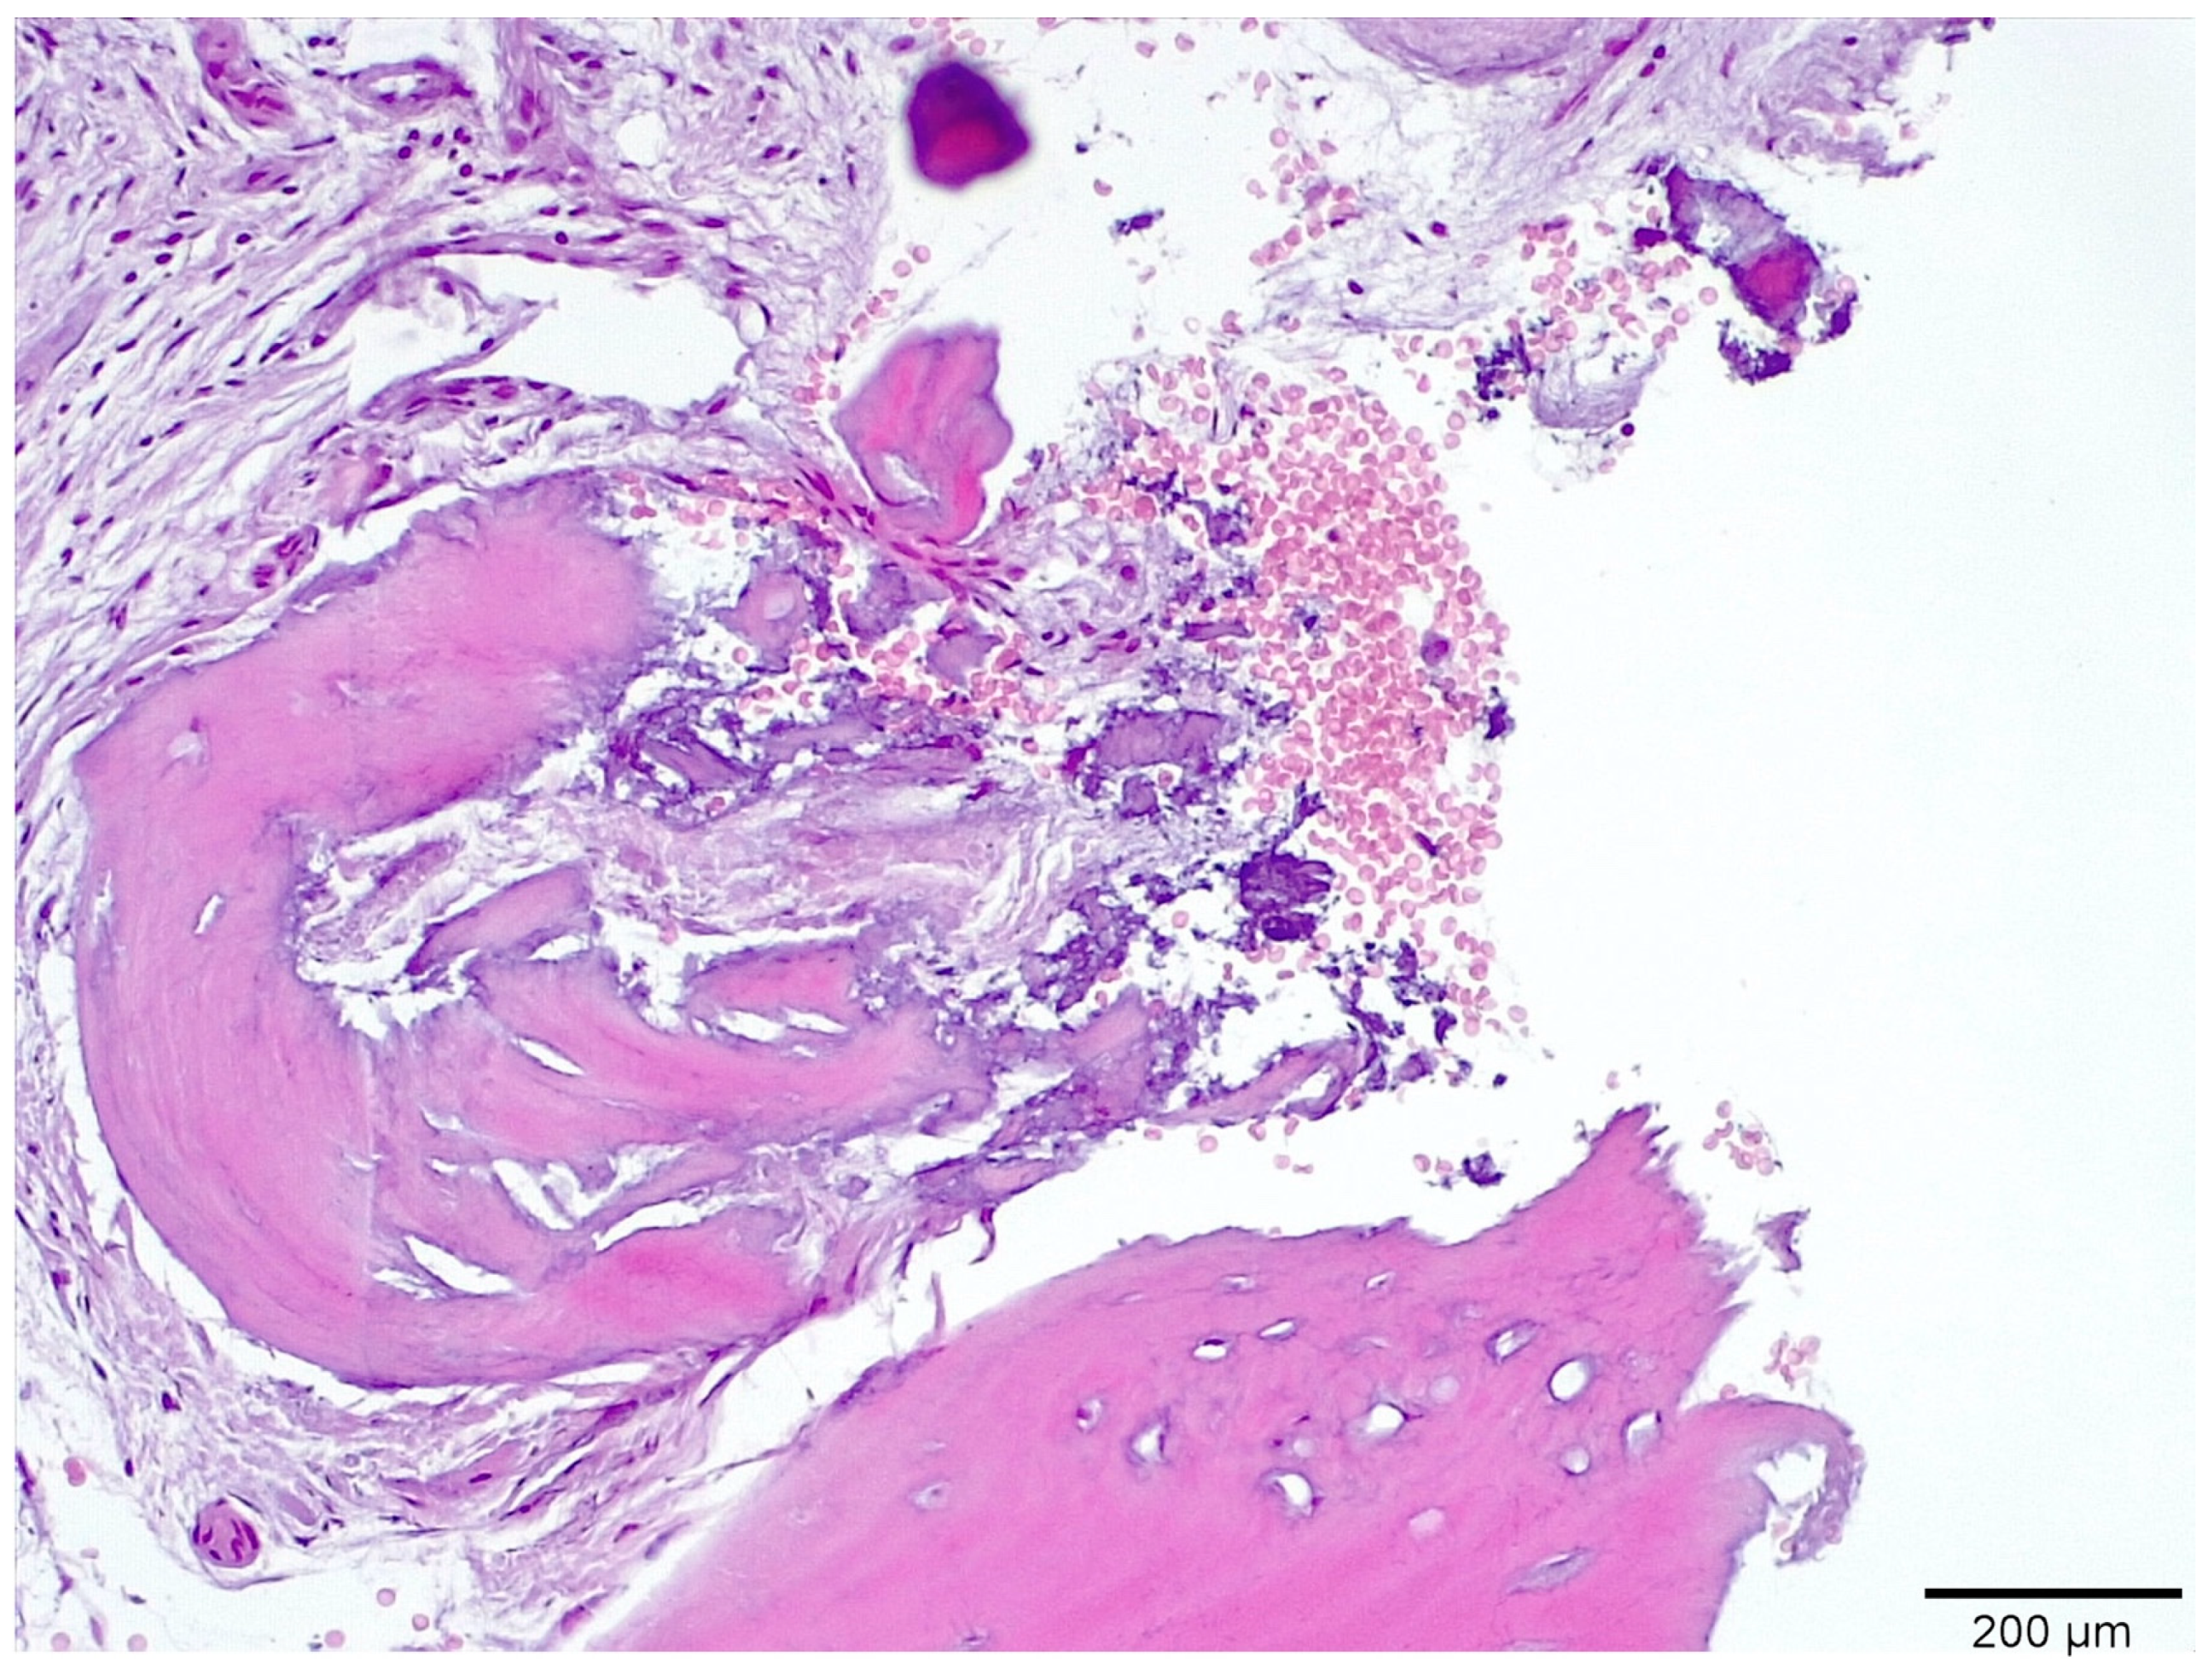

3.1. Histological Analysis Showed Signs of New Bone Formation at 60 Days

3.2. Histologic Data Obtained after Samples Analysis at 24 Months of Evaluation